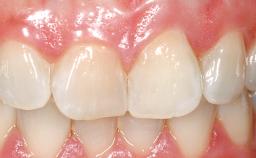

Immediate Placement of an Implant in a Maxillary Left Central Incisor Site

A 33-year-old female patient presented with an upper left central incisor that required extraction after a failed endodontic therapy. The tooth had been traumatized when the patient was a teenager and had undergone several endodontic treatments, including two apicectomy procedures. The patient was in good health and did not smoke. Clinical examination showed that the patient had a high lip line. In full smile, the gingival margins of the upper teeth were visible to the first molars. The gingival margins of central incisors 11 and 21 were only just showing. Examination of tooth 21 confirmed that the tooth was mobile and had hypererupted by 1 mm.

Prosthesis Type FDP

Soft Tissue Contour and Volume Slightly compromised